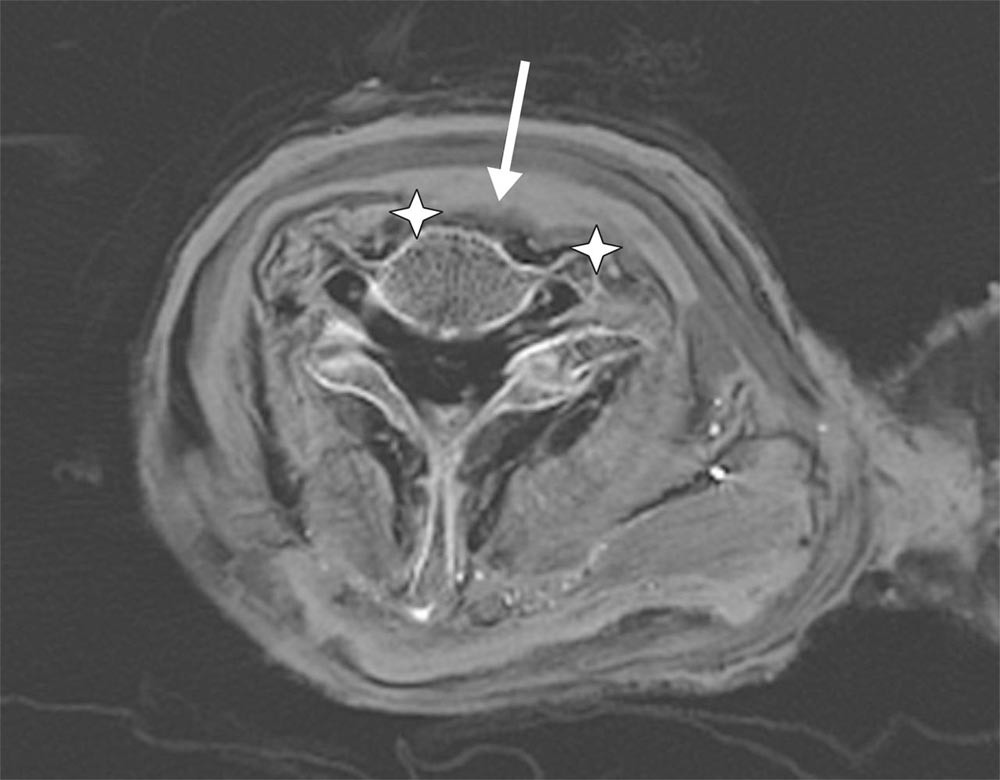

La investigación anterior llevó al equipo a descubrir la causa de la muerte de Ramsés III, un corte en la garganta con un cuchillo afilado, que cortó la tráquea y el esófago. Esto lo habría matado al instante.

El dedo gordo del Ramses III fue probablemente cortado de un hachazo, dijo Saleem Sahar, y se puede determinar en base a la forma de los huesos de los dedos amputados. Esta herida es anatómicamente distante del golpe mortal, y fue infligido con un arma diferente, el investigador explicó que debe haber habido otro asaltante.

Mientras que un atacante llegó por la parte delantera con un hacha o una espada, otro atacó por la espalda con un cuchillo o daga que lo degolló y le causo la muerte instantánea. Y, lo más probable es que los embalsamadores intentaron enmascarar el daño del pie del faraón asesinado, dijo Saleem.